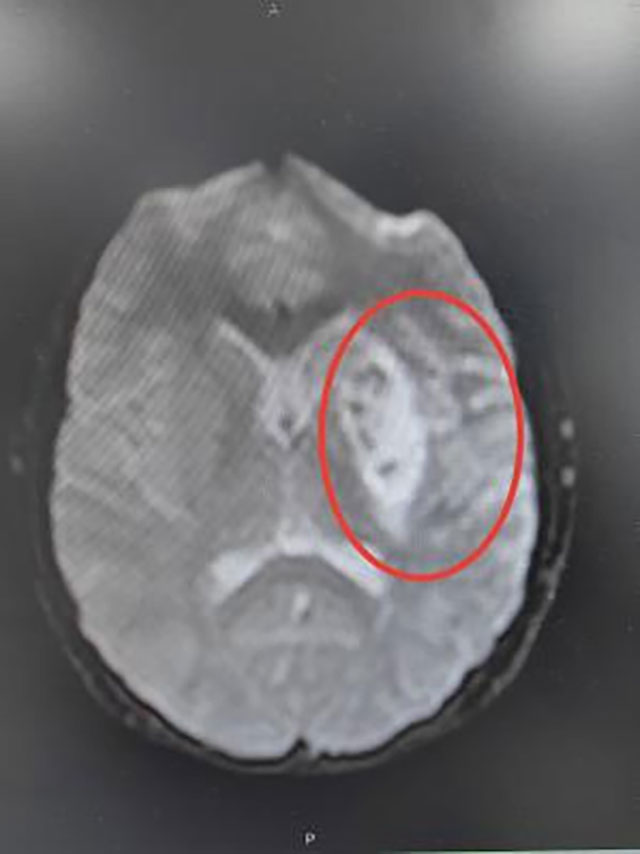

●头颅增强MRI:左侧额顶颞岛叶、基底节区、侧脑室旁及大脑中脚异常信号,部分病灶弥散受限,左侧外囊软化表现;

头颅MRI影像表现

最后考虑诊断为卵圆孔未闭合所致的脑梗死(心源性栓塞型),经中西医结合治疗后小王同学好转出院,并拟于后期接受卵圆孔未闭封堵术治疗。